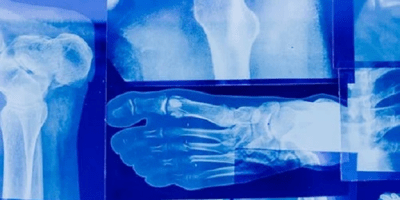

Stress Fractures: Risk Factors & Treatment